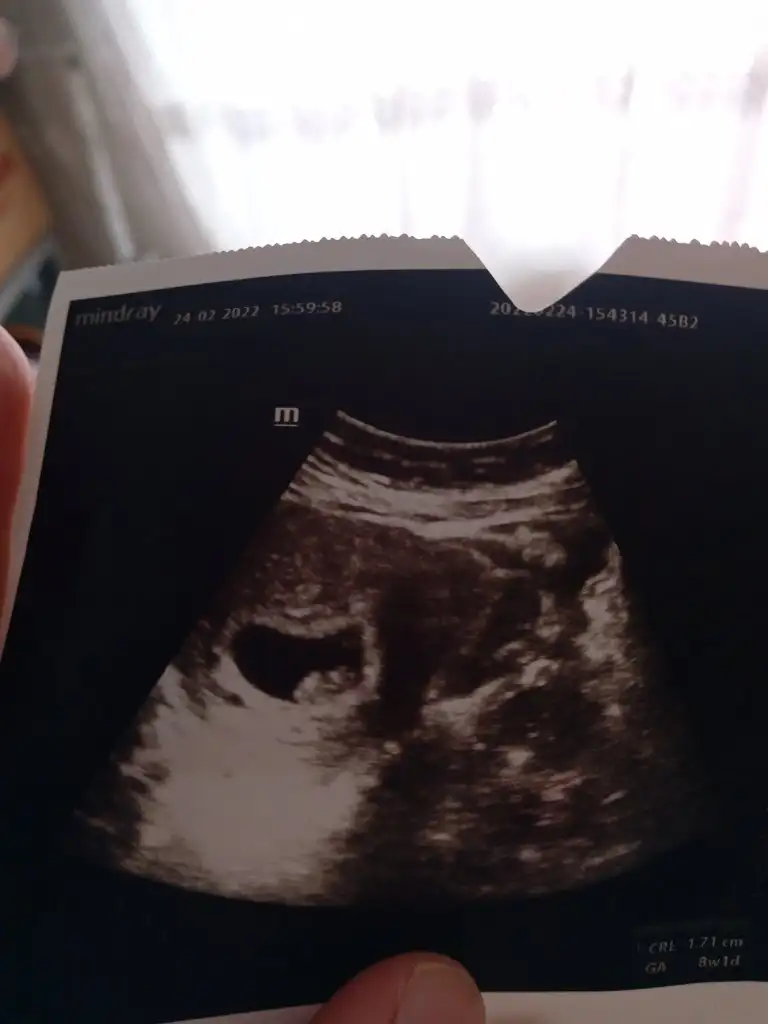

5 ve 14. haftaya kadar olan ultrason fotolarınızı paylaşın. Vajinadan mı yoksa karından mı çekildiğini ve kaç haftalık olduğunu da mutlaka belirtin.

Canım benimkini de yorumlar mısın 8 haftalık karından ultrason

Bebeğin konumuna bakarak mı cinsiyet söylüyorsun yoksa plesanta nın konumumukuzum iki görüntüde sana ait olmasına rağmen bebeğin pozisyon duruşu ikisinde de farklı ilk fotoda erkek ikincisinde kız pozisyonu var ama rahmin şeklide paralel duruyor bence kız öğrenince haber verirsen sevinirim![]()

Ama ramzi teorisi ne göre plesantaya göre cinsiyet belirleniyor çünkü 6-7-8 haftalık ultrason görüntüsünde bebek sürekli yer değiştiriyo plesanta ilk haftalarda belli olmuyo ama dikkatli bakarsan ultrason da beyaz parlak bir alan var orasını plesanta olarak baz alıyoruzerken dönemde plastayı görmek çok zor ama genellikle bebek neredeyse plesanta orada oluyor.

evet ben de o şekilde yaparak tahmin yürütüyorum zaten. bazen parlak alan dahi görünmüyor. o yüzden kadınlarımıza ileriki haftalarda da görüntü gönderin tahmin edelim birlikte diyorum.Ama ramzi teorisi ne göre plesantaya göre cinsiyet belirleniyor çünkü 6-7-8 haftalık ultrason görüntüsünde bebek sürekli yer değiştiriyo plesanta ilk haftalarda belli olmuyo ama dikkatli bakarsan ultrason da beyaz parlak bir alan var orasını plesanta olarak baz alıyoruz